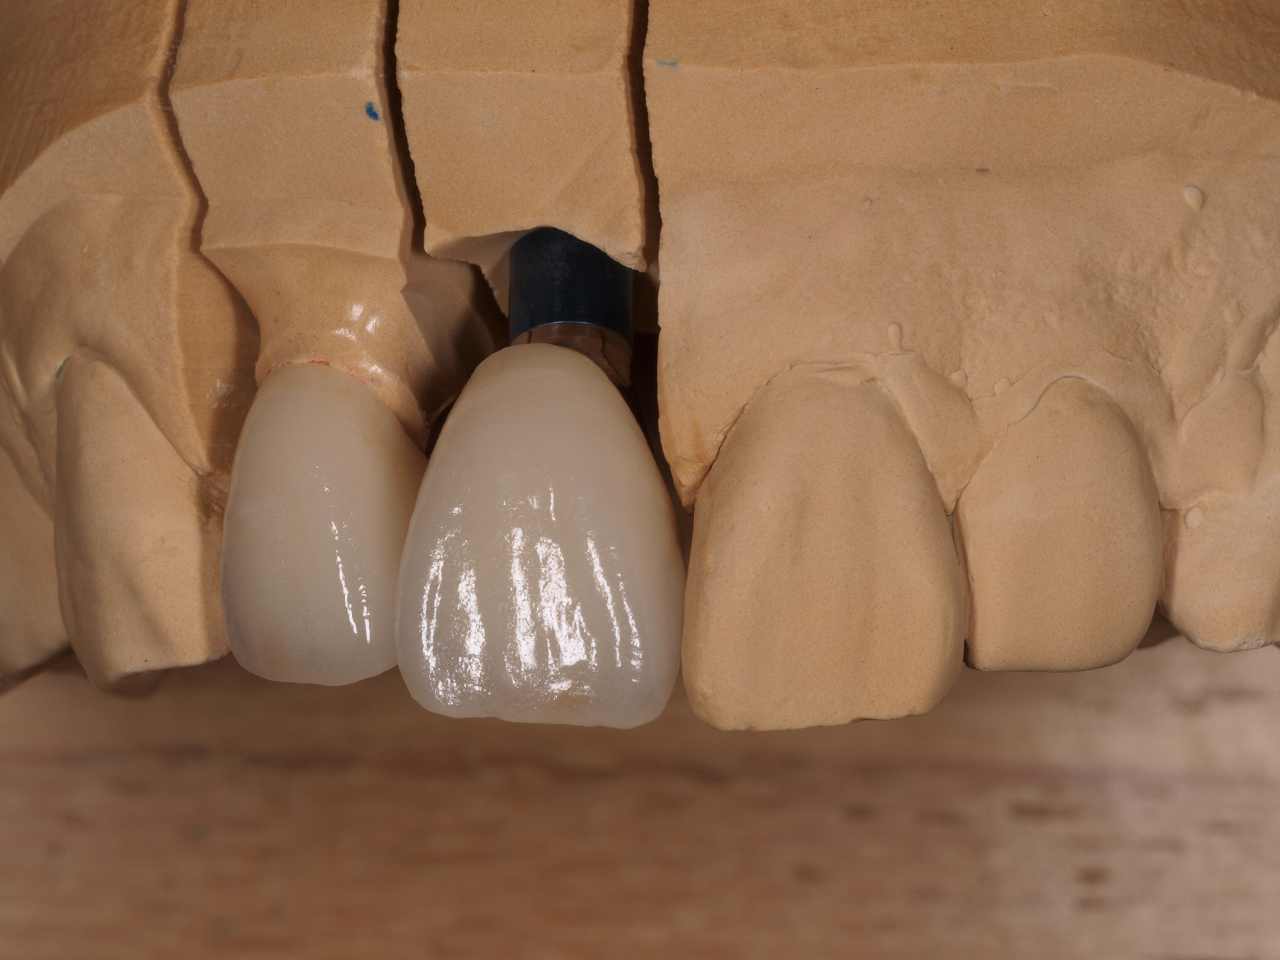

ジルコニアクラウンの色味をしっかりと出すためアバットメントは大き過ぎずの形態を技工所とも日々打ち合わせしています

プロビジョナルにてここまで歯肉形態は仕上がっています

最終補綴になります